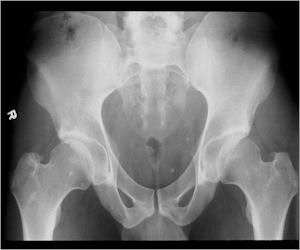

- Femoral neck most common but can occur in any bone and any site within a bone (metaphyseal, diaphyseal, epiphyseal; cortical, medullary and periosteal)

Plain X-Rays:

- Lucent nidus surrounded by a zone of marked sclerosis

- The nidus may demonstrate mineralization/ossification usually from the center outward that appears as a central zone of density within the nidus

- A nidus that is heavily ossified may blend in with the surrounding sclerosis and be difficult to detect on a plain x-ray.

- Periosteal bone is solid, rarely lamellated

- Cortical and subperiosteal osteoid osteomas are usually associated with much more reactive sclerosis than medullary tumors

- The periosteal reaction is continuous and often appears as cortical thickening (benign appearing reaction)

- Intracapsular osteoid osteomas are difficult to identify because there is no periosteum in the intracapsular region and hence a periosteal reaction does not occur.